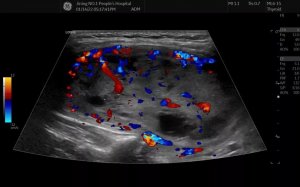

结节疯长至鸡蛋大小,济宁市第一人民医院成功开展巨大甲状腺结节热消融术

近日,济宁市第一人民医院超声医学科介入超声团队顺利完成一例巨...